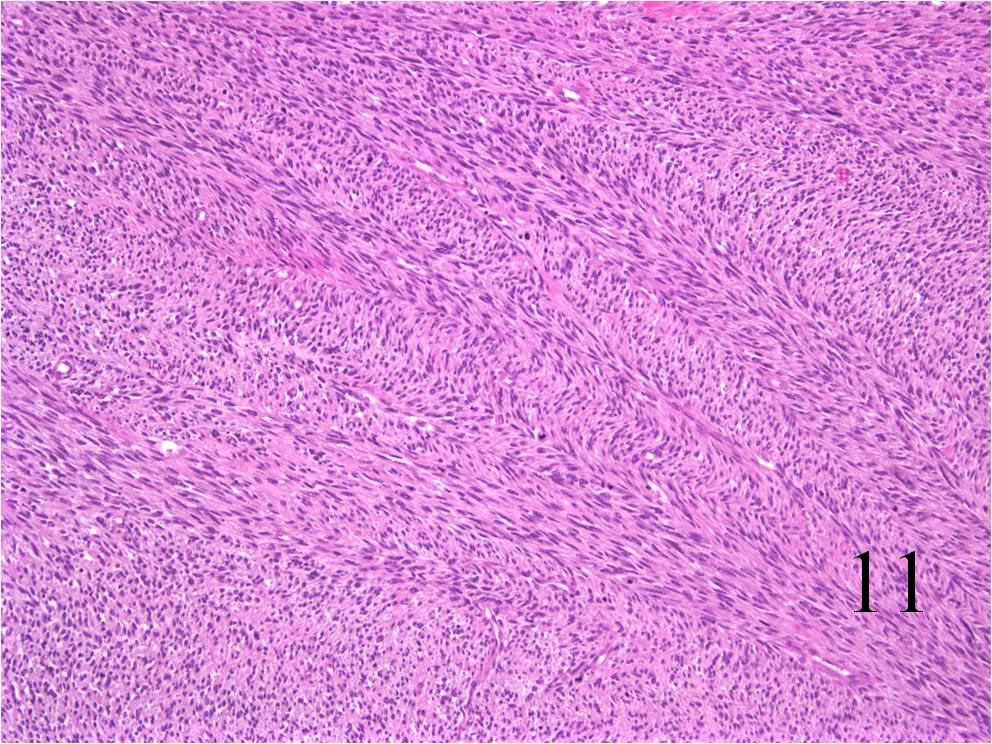

Microscopic

- Embryonal:

- Small round blue cells (Fig. 12-15)

- Round, oval, polygonal cells

- Fibrotic/myxoid stroma

- Rhabdomyoblast: well differentiated will have cross striations